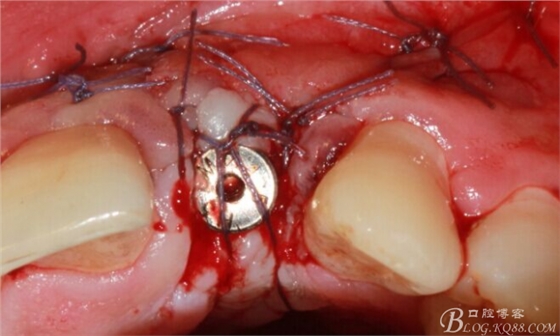

減張縫合。自我感覺一切OK。囑其近期不可劇烈活動(dòng),也不要總想著為國足報(bào)仇。